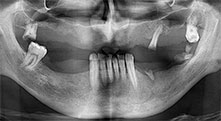

Bratu: Wir bevorzugen Knochenentnahmen von der Linea obliqua externa des posterioren Unterkiefers, nicht aus der interforaminalen Region. Nach der Weichgewebsinzision verwenden wir die neuen Sägen, um den Umfang der Knochenentnahme zu definieren. Wir erledigen damit in fast 80 Prozent der Fälle auch die gesamte Präparation. Zusätzlich verwenden wir eventuell andere Piezo-Instrumente und zuletzt einen Meißel, um den Block zu mobilisieren. Das ist für uns eine sehr effektive Operationstechnik.

Bratu: Wir augmentieren im seitlichen Unterkiefer gern mit der Sandwich-Technik. Dabei wird ein Knochendeckel mit der Piezosäge präpariert und das krestale Fragment mit Mikroschrauben fixiert. Dazwischen platzieren wir eine Mischung aus autologem Knochen und xenogenem Knochenersatzmaterial. Das funktioniert sehr zuverlässig. Bei Kieferkammspaltungen im Unterkiefer sollten Sie nie auf ausreichend dimensionierte vertikale Schnitte verzichten. Sonst kann der Knochen leicht frakturieren.